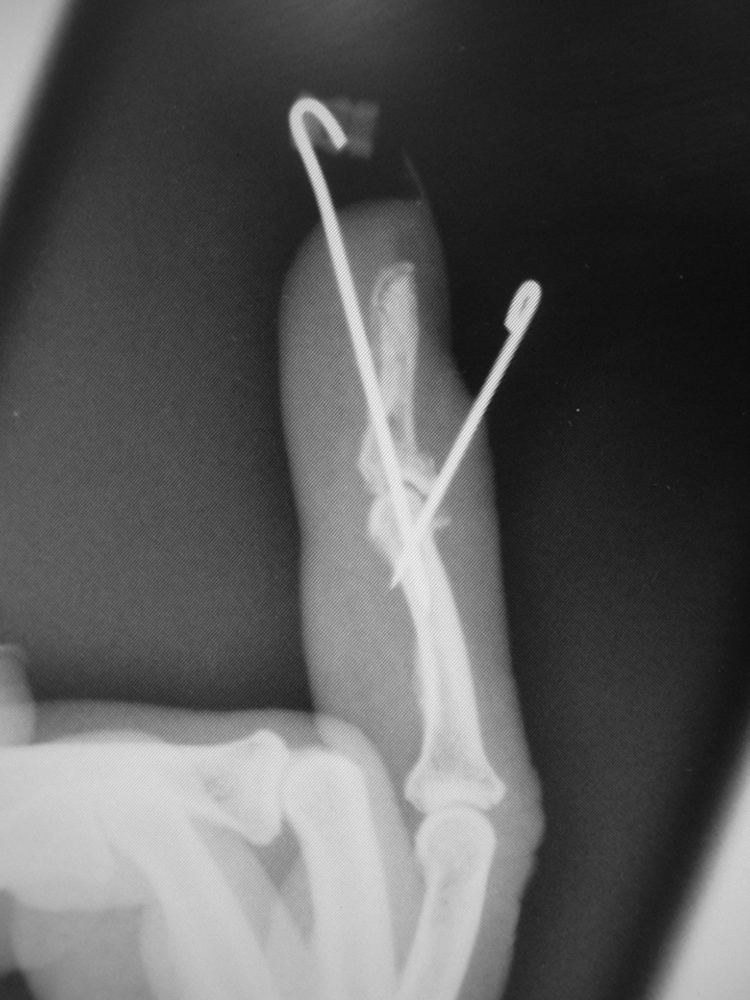

In volar fractures the flexor digitorum profundus (FDP) pulls the attached fragment away from the distal phalanx and will need surgical reattachment and a flexor tendon rehabilitation regimen. In dorsal fractures the fragment is held in place by the extensor tendon, whilst the FDP pulls the distal phalanx volarly, the latter resulting in a bony mallet or a mallet fracture. If surgery is required and the fragment is dorsal, Ishiguro’s method of fixation is a good solution. The dorsal wire supports the dorsal fragment and is placed first with the DIP joint in flexion; the fracture dislocation is then reduced and the longitudinal wire is placed under image-intensifier (II) guidance ( Fig. 56.7 ). In volar fractures the fragment, if large enough, can be secured with a screw. If, however it is too small to withstand instrumentation, then the FDP can be fixed to the distal phalanx by bony anchors, pull-out sutures, or by sutures passed through the distal phalanx transversely, using a white needle drilled through the bone. The DIPJ will become somewhat stiff whatever you do.